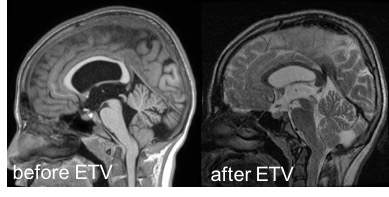

le traitement de l’hydrocéphalie

c’est la première chose à faire s’il les ventricules sont larges et que le plancher du 3ème ventricule est abaissé. cette décision est d’autant plus justifiée qu’il existe un problème hydraulique comme une syringomyélie. on réalise en première intention une ventriculo-cisternostomie endoscopique.

c’est la surveillance ultérieure, clinique et radiologique, qui fera décider, ou non, d’une geste de seconde intention sur la charnière cranio-cervicale.